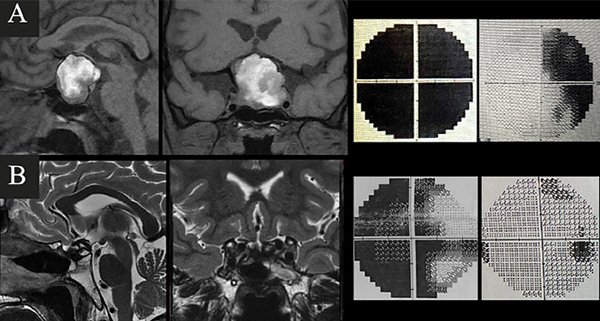

Caso 1. A. Preoperatorio. Varón de 63 años, hipertenso y antiagregado con AAS que consultó por cefalea, náuseas, vómitos y síncope. Al examen físico presentaba disminución de la AV en ojo izquierdo + ptosis palpebral y midriasis izquierdas. En la TC y RM de cerebro e hipófisis se evidenciaba una lesión selar con componente hemorrágico y edema de la vía óptica. El CVC evidenciaba hemianopsia temporal izquierda y cuadrantopsia superior derecha. B. Postoperatorio. RM que demuestra resección completa y CVC normal.

Caso 3. A. Preoperatorio. Paciente de 31 años, anticoagulado por TEP derivado de otro hospital por disminución aguda de la visión. La RM de hipófisis evidenciaba una lesión selar-supraselar voluminosa con un gran contenido hemorrágico. El CVC objetivaba amaurosis derecha y hemianopsia izquierda. B. Postoperatorio. RM que demuestra resección completa de la lesión y CVC con mejoría parcial.